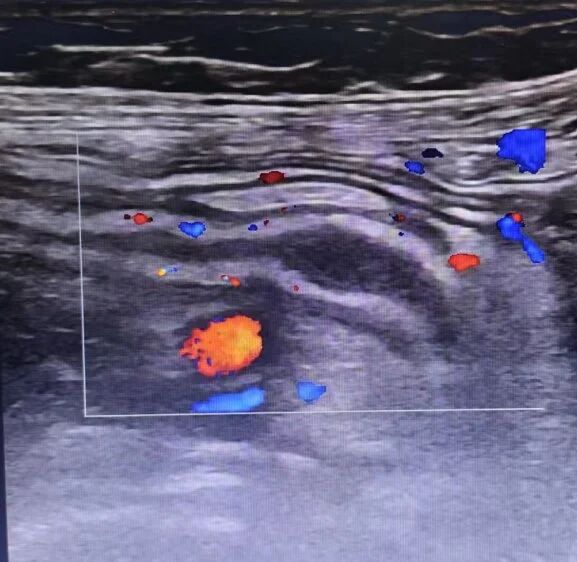

左侧输尿管上段结石超声影像

1.泌尿系结石:尤其对肾结石、输尿管及膀胱结石显示清晰,并能发现结石引起的肾积水。